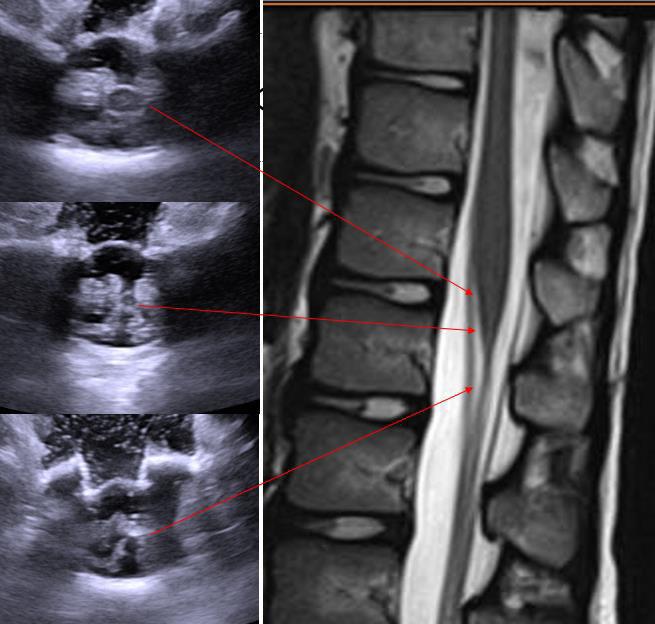

SDR involves surgically accessing the spinal cord (typically in the lumbosacral region, L2 to S1 or S2).The dorsal (sensory) nerve roots are carefully identified and then divided into smaller bundles called rootlets.